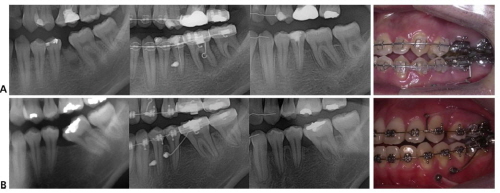

연구팀은 2004년 1월 1일부터 2011년 12월 31일까지 병원을 찾아 교정치료를 받은 16세 이상 환자군을 연구대상 집단으로 선정했다. 모두 37명(남성 18명, 여성 19명)으로, 총 51개의 상실치아에 대한 교정치료가 연구관찰 됐다.

평균 23.2세인 환자군은 31.7개월의 치료기간을 보였으며, 잇몸 위 치아는 평균 4.97mm를 움직였고 잇몸 속 치아 뿌리는 평균 8.64mm를 이동해 잇몸 위 치아보다 치아 뿌리가 2.81배 더 이동한 것으로 측정됐다.

연구팀은 교정치료로 치아 뿌리가 이동함에 따라 발생할 수 있는 치조골 소실 정도와 교정치료 완료 후 치근의 길이를 측정했다.

전체 연구대상(51개 치아)군의 약 80%에 육박하는 40개 치아에서 치조골 소실 정도가 1mm 미만인 것으로 나타났으며, 치근의 길이 또한 1mm 이내로 변화해 환자가 교정된 자연치아를 평생 이용하는데 문제가 없는 것으로 나타났다.